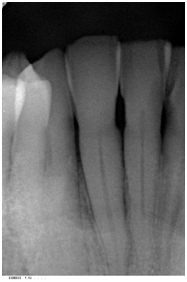

A 72 year-old white male was referred due to an isolated increasing probing depth on the disto-facial aspect of the mandibular right lateral incisor which had an initial PD of 10 mm with BOP (Table 2). Increase in probing depth is illustrated in the clinical photo (Figure 6). The patient was seen for a comprehensive periodontal examination and a periodontal maintenance visit after scaling and root planing was previously performed. His oral hygiene and plaque control was very good and no local factors were detected at that time. Radiographic evaluation revealed a slight radiolucency on the distal of tooth #26 (Figure 7).

Figure 7 Pretreatment radiograph of tooth #26 revealed a slight radiolucency on the distal aspect.